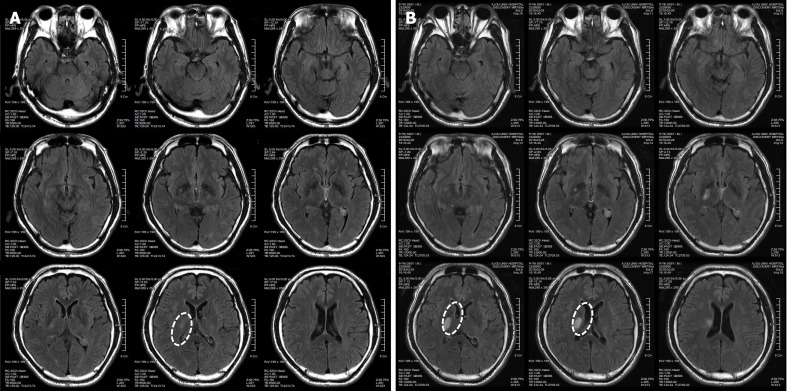

患者于2018年2月17日至18日出現(xiàn)暫時(shí)性無(wú)力癥狀,早上醒來(lái)后突發(fā)急性中風(fēng),導(dǎo)致左上肢和下肢癱瘓。患者在大學(xué)醫(yī)院急診室被診斷為Rt紋狀體囊性梗死(圖1A)。他于2018年3月2日出院,僅接受了阿司匹林處方,因?yàn)楦鶕?jù)腦計(jì)算機(jī)斷層掃描 (CT) 掃描,他的腦血管正常,盡管他的病情在住院期間惡化(圖1)。出院當(dāng)天,他被送往康復(fù)專(zhuān)科醫(yī)院接受長(zhǎng)期康復(fù)治療。然后他于2018年3月13日來(lái)韓國(guó)首爾生物美容與健康公司 (bBHC)-干細(xì)胞治療與研究所 (STRI)接受干細(xì)胞治療。